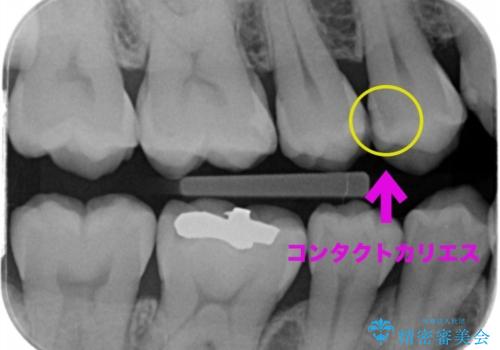

歯と歯の間の虫歯(コンタクトカリエス)

- 虫歯がないかチェックしてほしいとの事で来院。

レントゲンで歯と歯の間に虫歯(コンタクトカリエス)があったので

拡大鏡下で虫歯を全て除去して、e-maxインレーにて治療しました。

コンタクトカリエスについて

コンタクトカリエスは歯と歯の間にできる虫歯で

歯ブラシでは磨くことはできません。

毎日歯間ブラシやフロスを使用することにより予防することができます。